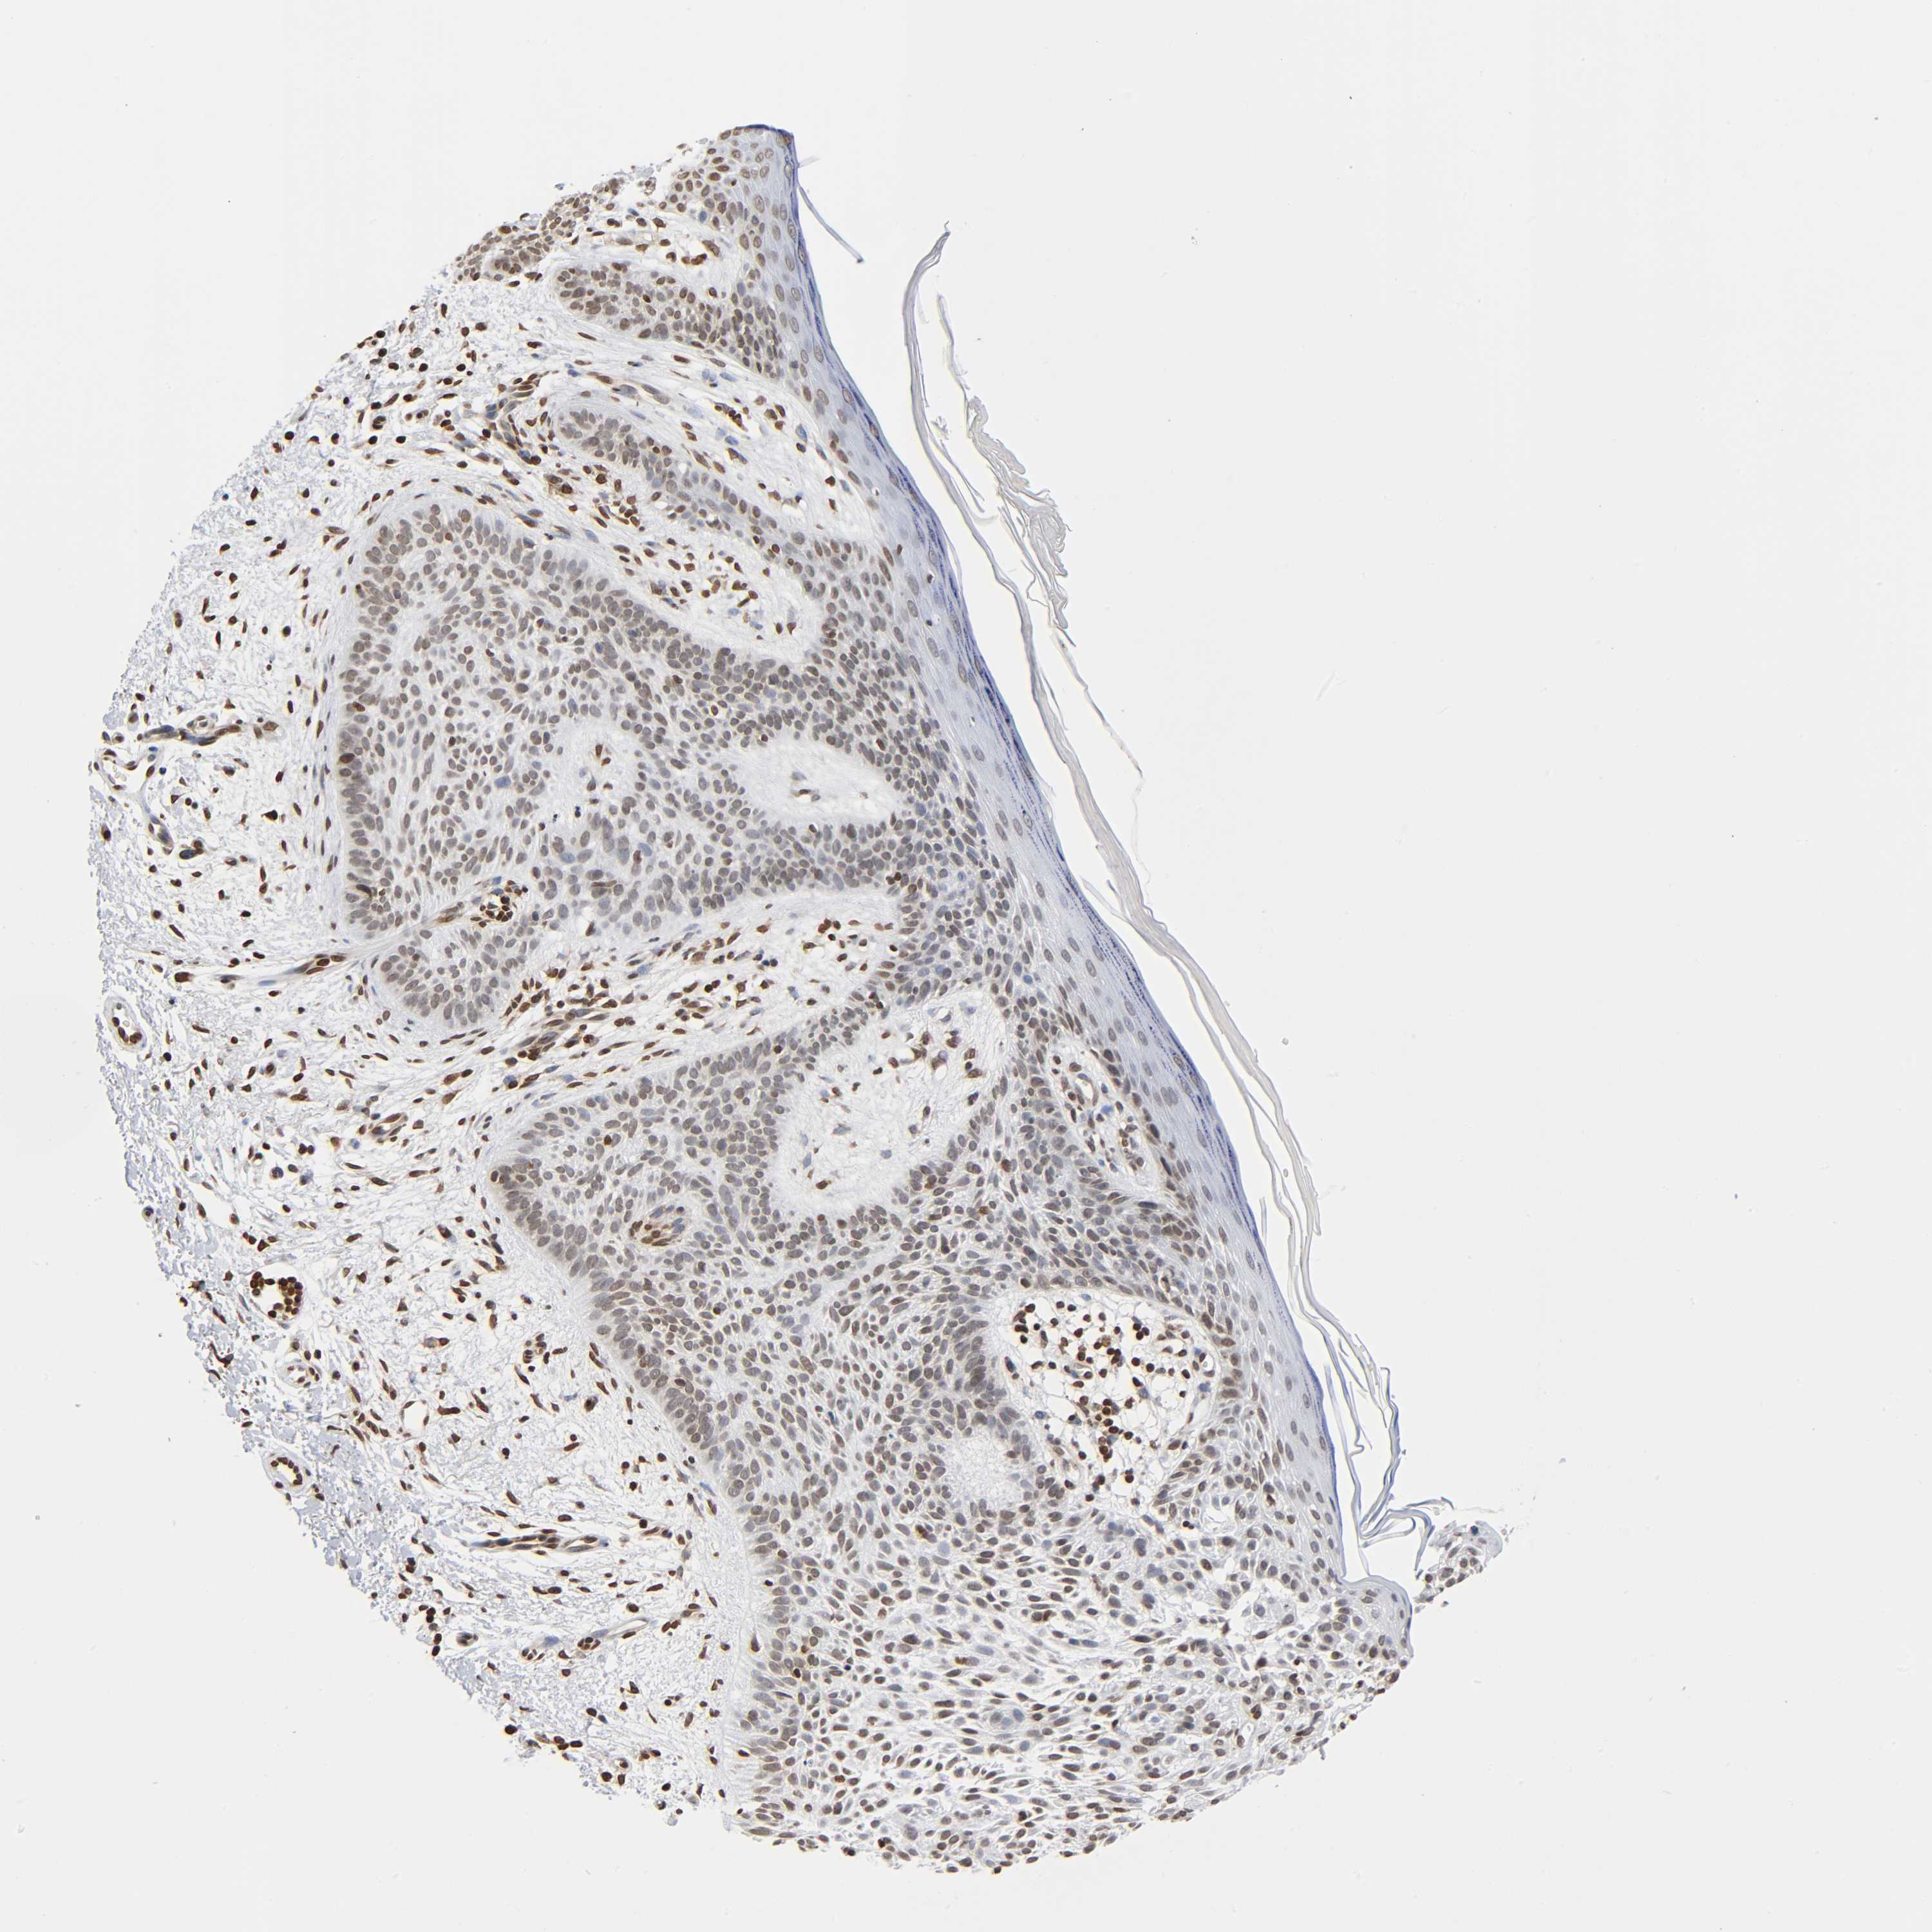

Basal cell and squamous cell cancer

SKIN CANCER - Protein expressioni

A mouse-over function shows sample information and annotation data. Click on an image to view it in a full screen mode. Samples can be filtered based on level of antibody staining by selecting one or several of the following categories: high, medium, low and not detected. The assay and annotation is described here.

Antibody stainingi

Antibody staining in the annotated cell types in the current human tissue is reported as not detected, low, medium, or high, based on conventional immunohistochemistry profiling in selected tissues. This score is based on the combination of the staining intensity and fraction of stained cells.

Each image is clickable and will lead to virtual microscopy that enables deeper exploration of all samples and also displays staining intensity scores, fraction scores and subcellular localization as well as patient and tissue information for each sample.

Antibody HPA004203

Staining

High

Intensity

Strong

Quantity

>75%

Location

Nuclear

Basal cell carcinoma